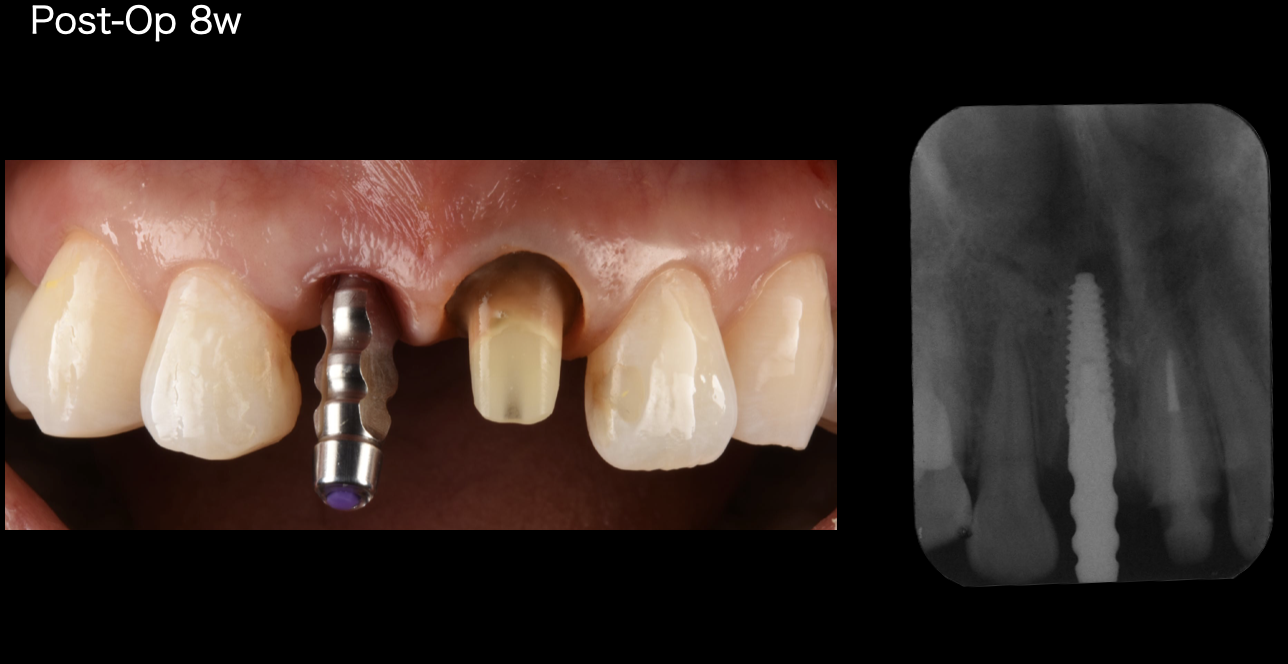

手術から8週間。二次安定の確認が取れたので、最終的な歯の型取りをします。